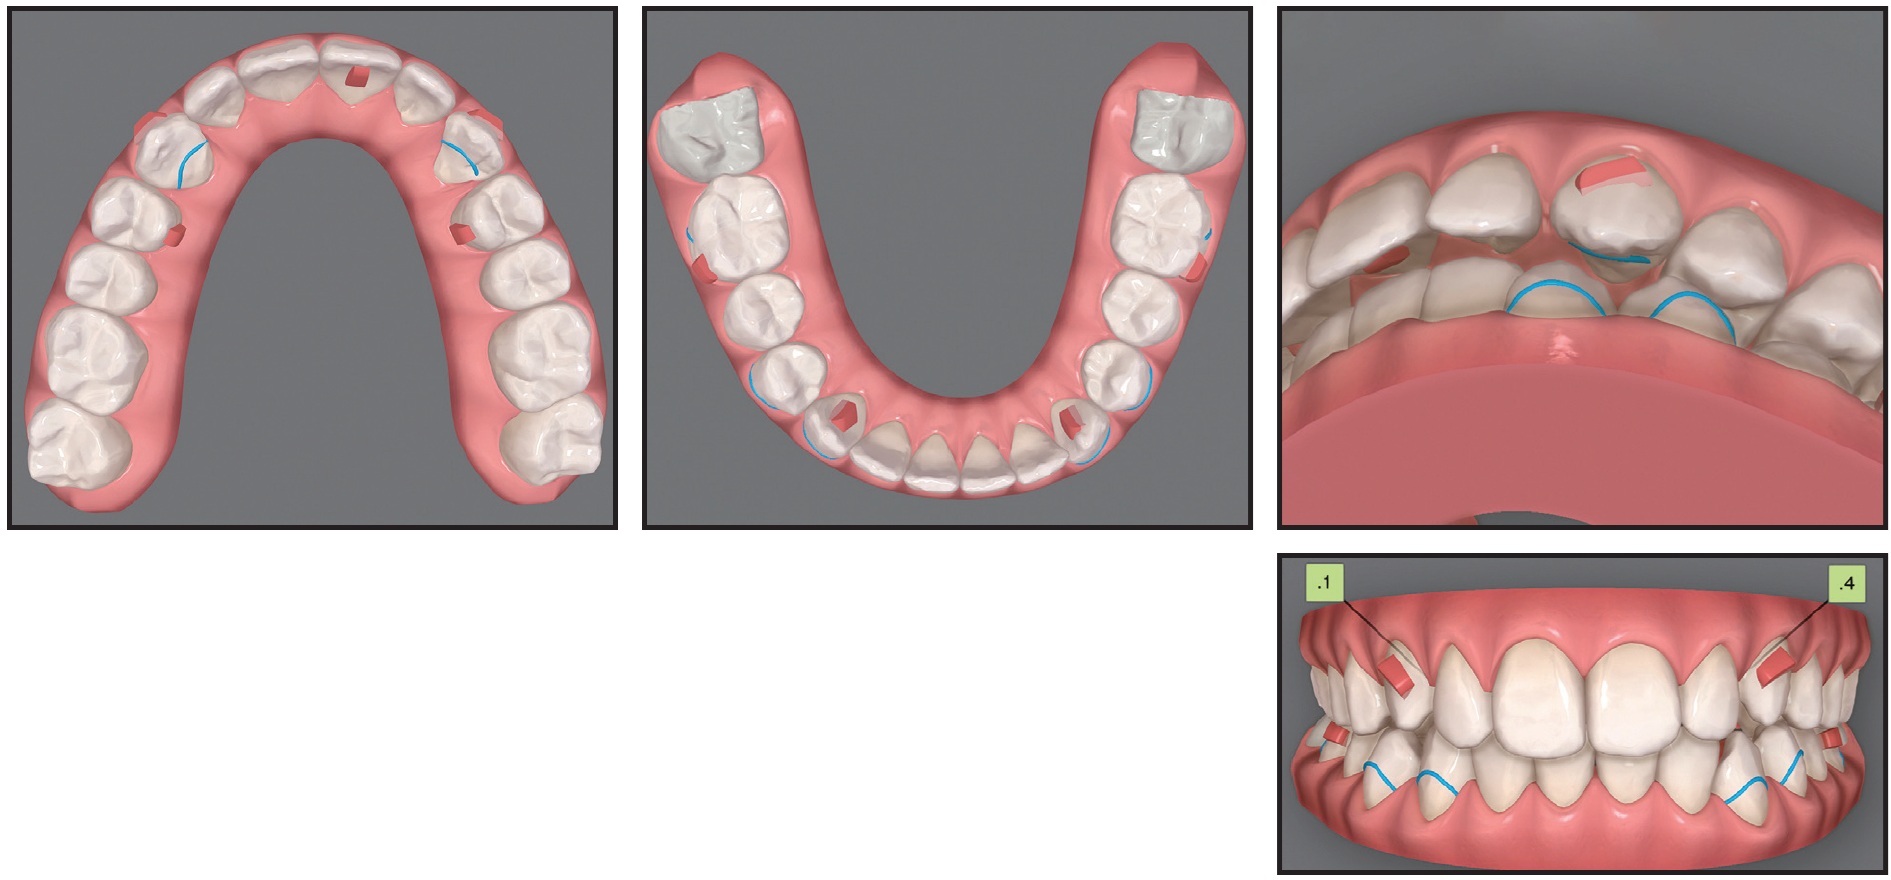

Case 1: Applying an Extrusive Traction Force

A 22-year-old female was referred by her general dentist for treatment of retained upper deciduous canines (Fig. 1A). She had a mildly convex soft-tissue profile, excessive lower anterior facial height, and an obtuse nasolabial angle. The smile arc was consonant, with 90% gingival display, but some lip incompetence was noted. The lower midline was deviated to the left of the facial midline. The overjet was 4mm, and the overbite less than 1mm. Mild Class II molar relationships were present on both sides.

Fig. 1 Case 1. 22-year-old female patient with bilaterally impacted upper canines before treatment (continued in next image).

The panoramic radiograph showed that both upper canines were impacted and slightly overlapping the roots of the lateral incisors. Cone-beam computed tomography (CBCT) evaluation revealed a palatal position of the left canine and a mid-crestal position of the right canine (Fig. 1B).

Fig. 1 (cont.) Case 1. 22-year-old female patient with bilaterally impacted upper canines before treatment.

Considering the patient’s age and the locations of the impacted canines,14 the best treatment option was determined to be surgical exposure followed by orthodontic traction to bring the teeth into the arch. Invisalign clear aligners were selected to meet the patient’s preference for esthetic treatment. Additional objectives were to align the teeth and correct the Class II relationship and midline deviation. Sequential distalization would be performed in the maxillary arch (3mm on the right side and 4mm on the left), and Class II elastics would be used to prepare space for the canine and correct the Class II relationship (Fig. 2).

Fig. 2 Case 1. ClinCheck* superimposition of initial (white) and planned (purple) tooth positions for correction of Class II relationships using sequential distalization and Class II elastics.